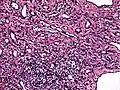

Micrograph of a kaposiform hemangioendothelioma with "glomeruloid" nodules of endothelial cells.

• Kaposiform hemangioendothelioma (also known as "Infantile kaposiform hemangioendothelioma"[3]) is an uncommon vascular tumor, first described by Niedt, Greco, et al. (Hemangioma with Kaposi's sarcoma-like features: report of two cases.(Niedt GW, Greco MA, Wieczorek R, Blanc WA, Knowles DM 2nd. that affects infants and young children, with rare cases having also been reported in adults. Pediatr Pathol. 1989;9(5):567-75.)[2]:596[3]:1782